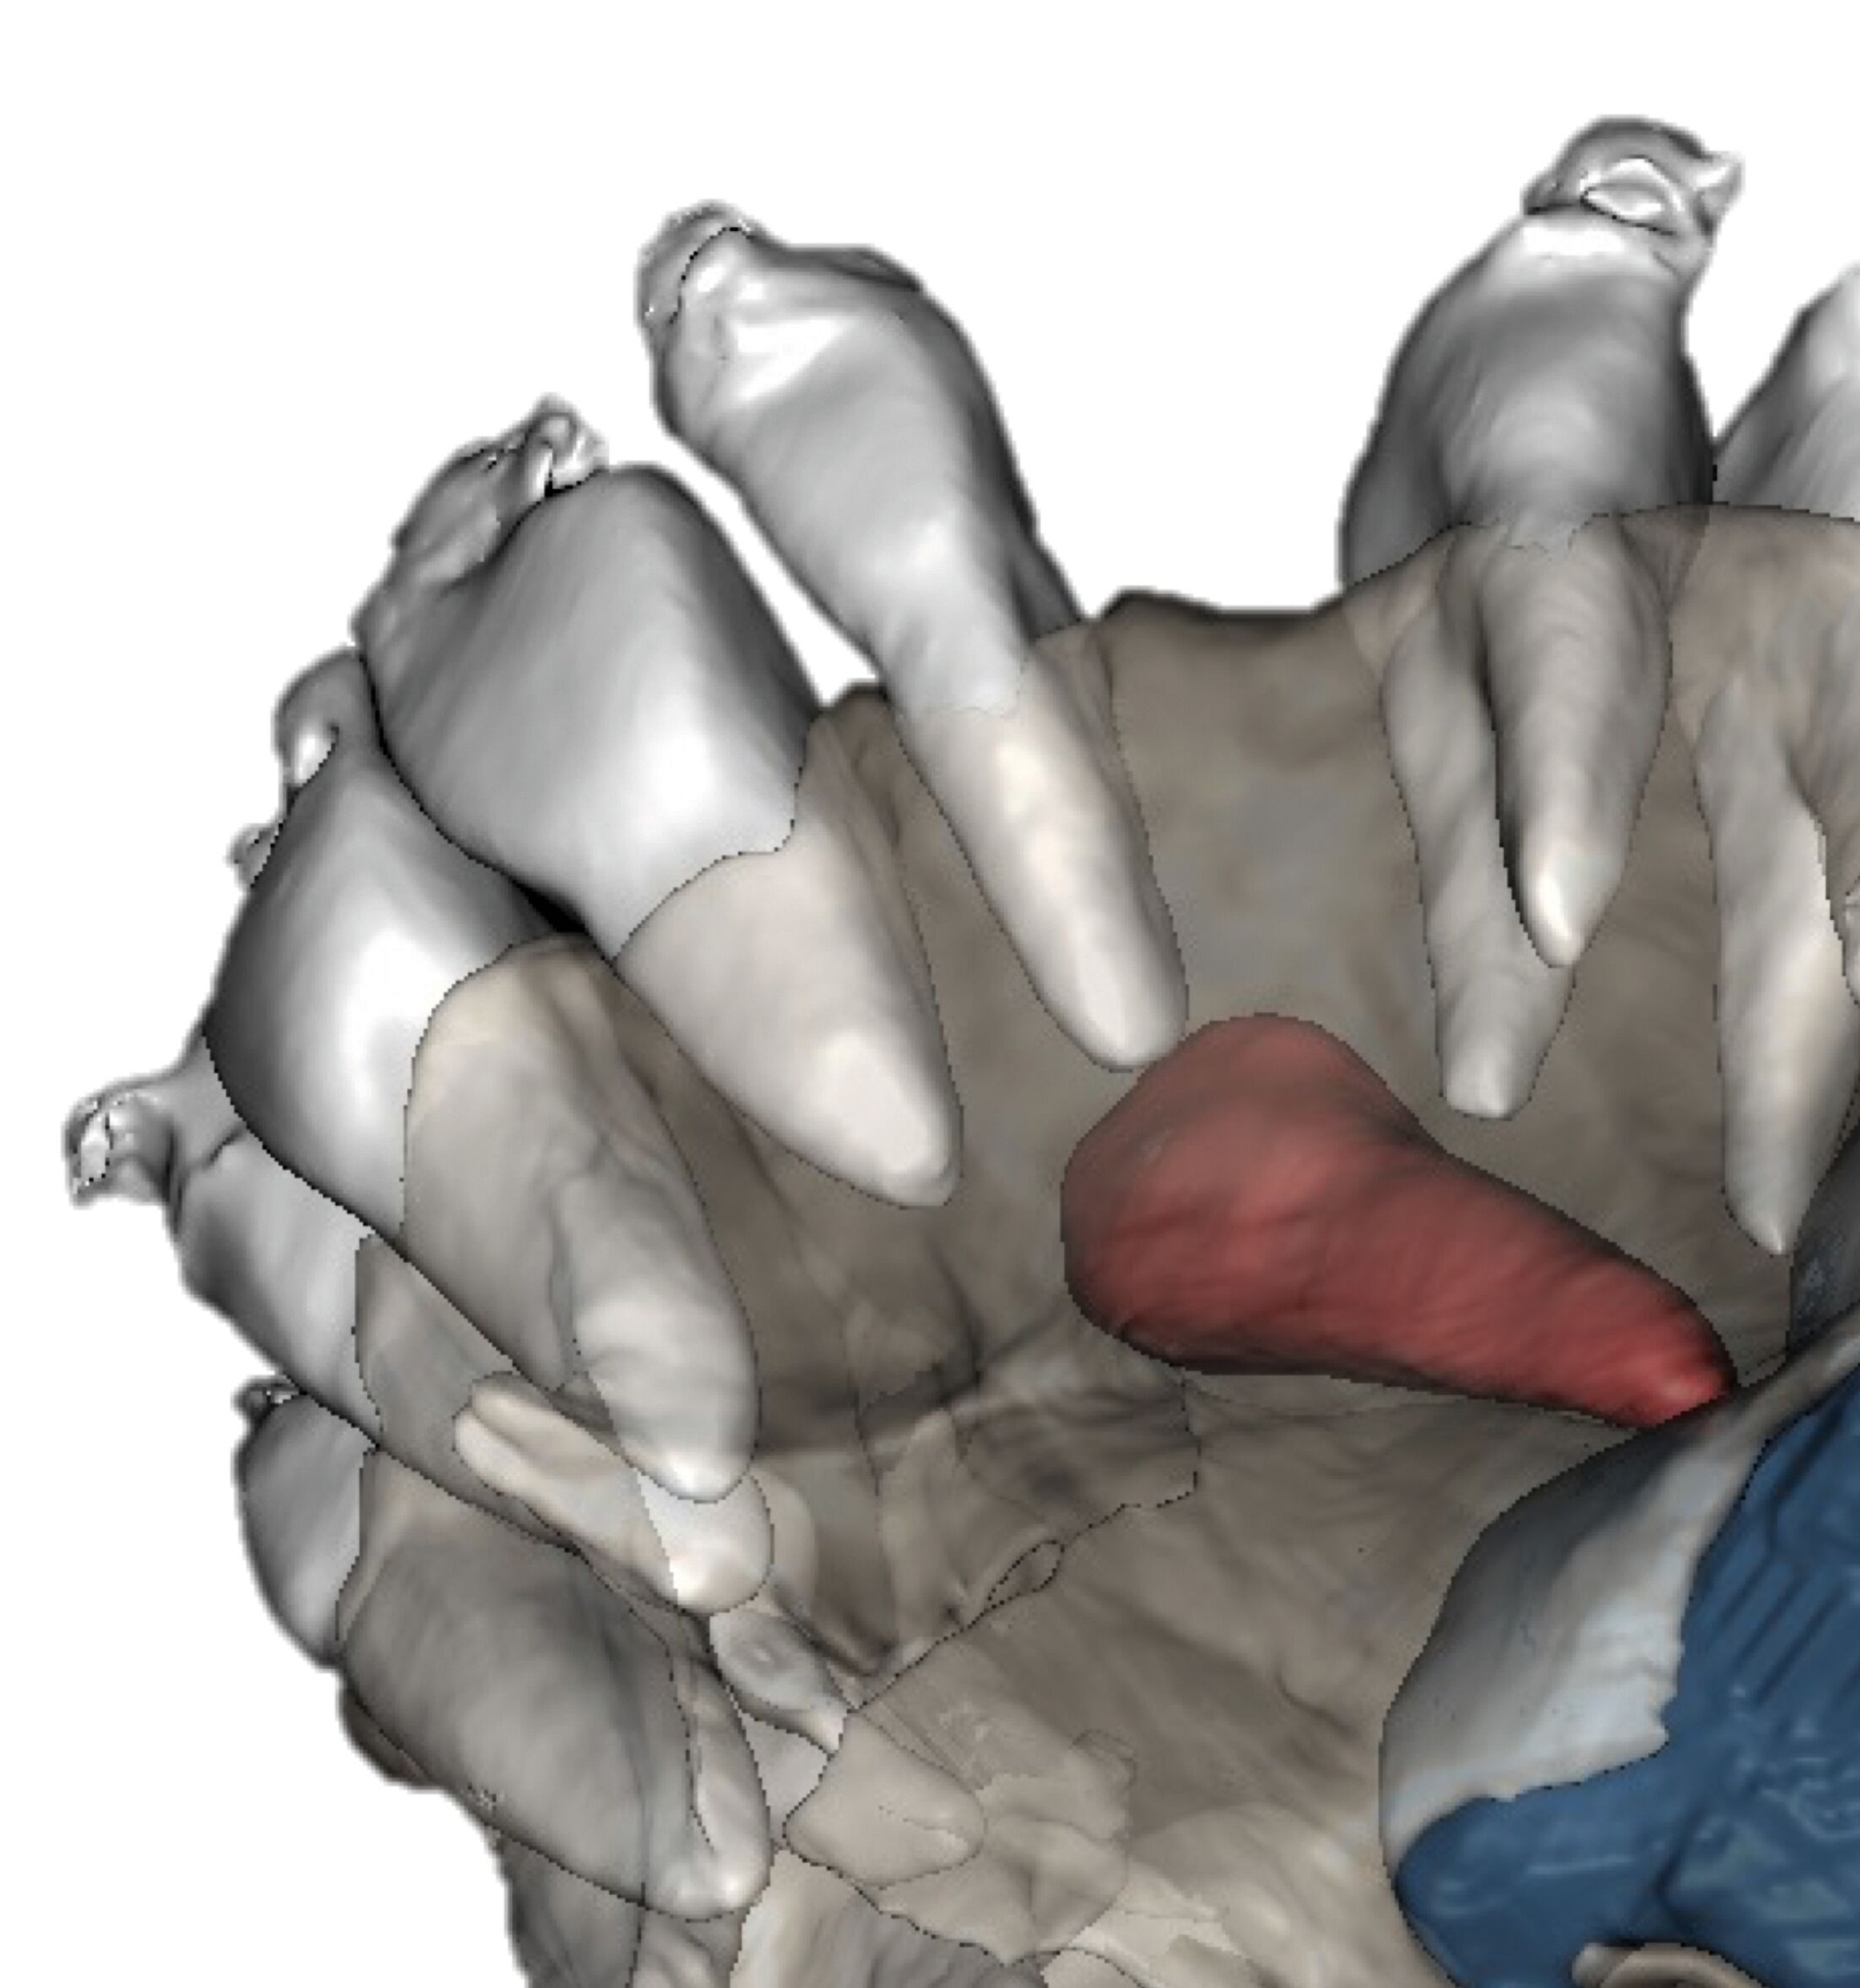

In Absprache mit dem/der zahnärztlich beziehungsweise chirurgisch tätigen Kollegen/in kann die Kieferorthopädie durch Umsetzung verschiedenster 3-D-gedruckter Elemente eine Hilfe in interdisziplinären Behandlungen bieten. Am Beispiel der Zahntransplantation ermöglicht der 3-D-Druck zuvor im DVT segmentierter Zähne eine passgenaue Vorbereitung des Transplantationsbettes (Abbildung 6a). 3-D-gedruckte Zähne können darüber hinaus als Lückenhalter während der kieferorthopädischen Behandlung dienen (Abbildung 6b), bevor eine definitive Versorgung durch den/die zahnärztliche/n Kollegen/in erfolgt.